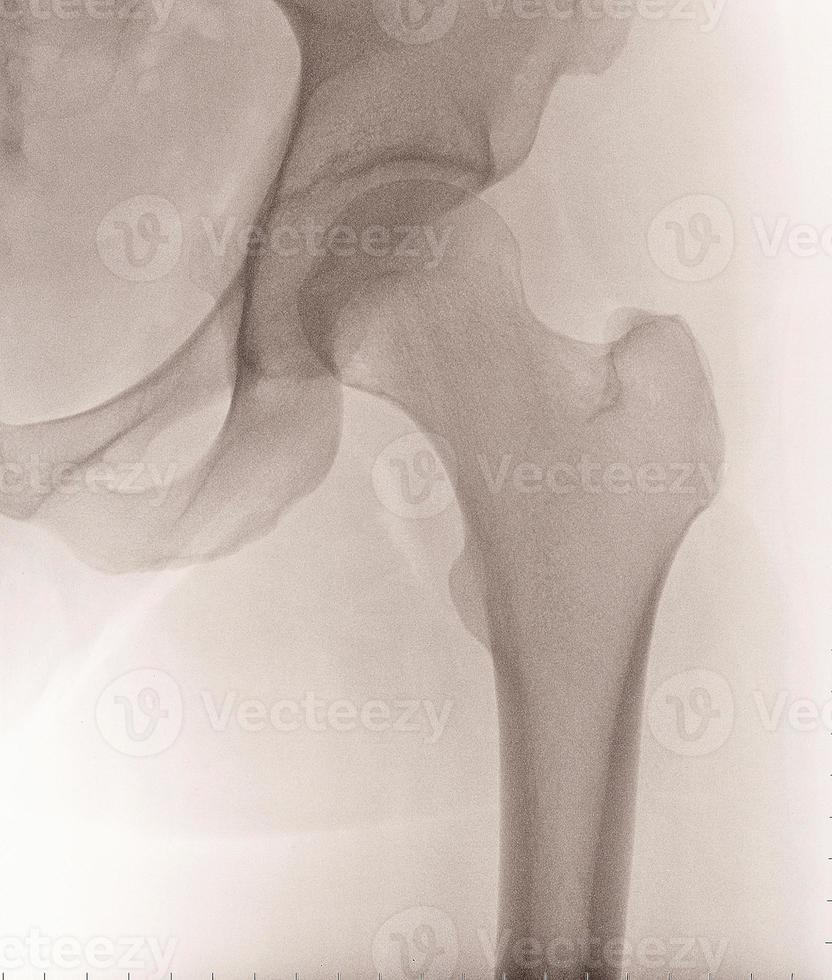

From www.vecteezy.com

Female Left Hip XRay 17402725 Stock Photo at Vecteezy Types Of Hip X Ray Views    radiographic protocols designed for the hip can vary based on the clinical scenario and personal preference of the referring physician. The series is requested for.   imaging of the pelvis can be required following minor or major trauma and for nontraumatic painful conditions. The series is requested for a.   the hip series is comprised of an anteroposterior (ap). Types Of Hip X Ray Views.